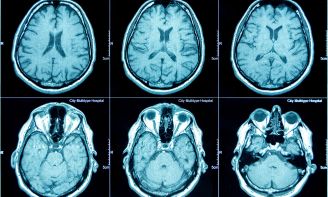

Redefining Early Diagnostic with Metabolic Imaging

The visualization of human metabolism allows for the detection of metabolic-related diseases in their earliest stages. By observing the metabolic processes at a cellular level, we can identify conditions such as cancer long before severe symptoms appear.

This breakthrough in early detection not only enables the identification of diseases at their most treatable stages but also accelerates treatment effectiveness. With real-time visualization of treatment responses, the progress of therapy can be directly monitored, ensuring faster and more effective intervention.